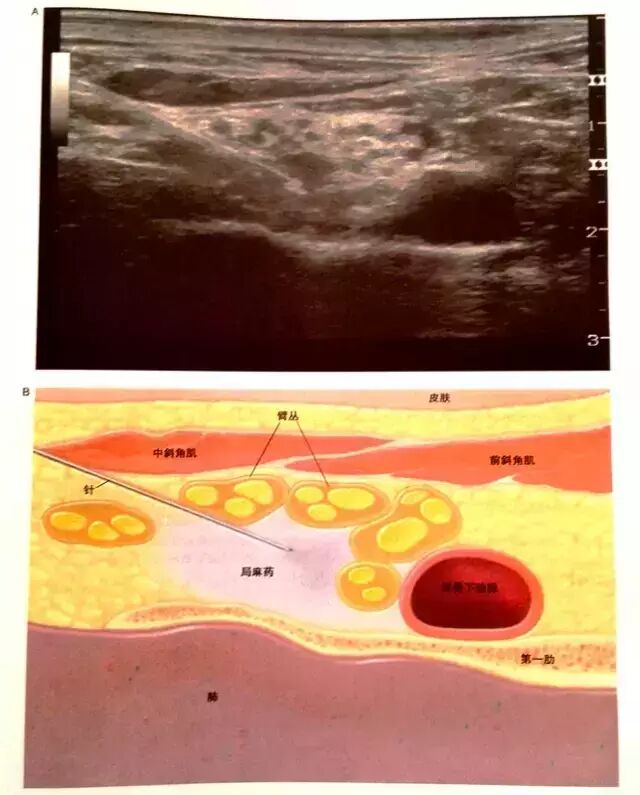

超声图像特点

锁骨上臂丛神经,臂丛神经横断面呈低回声,黑色,周围是三角形的高回声的神经鞘(白色),内侧是圆型搏动环低回声锁骨下动脉,锁骨下动脉位于高回声的第一肋上方。神经鞘内的神经分支形成5-6个黑色圆环,周围被高回声环(纤维膈)包裹分隔成独立的室(这就是锁骨上臂丛神经阻滞单点注药起效慢和阻滞不全的原因)。斜角肌肌肉呈低回声(黑色),下方也可见到呈高回声(白色)的胸膜顶神经分支情况。

1、超声监视下,从探头的外侧约1cm处进针。

2、于浅表神经束之间,注入局麻药5-8ml,神经束可因药液的注入而分散开。

3、继续进针并注射药液,最后进针至锁骨下动脉旁的臂丛神经下干前、后两股间注入局麻药,过程中实时观察局麻药的扩散情况。

4、神经束被药液浸润